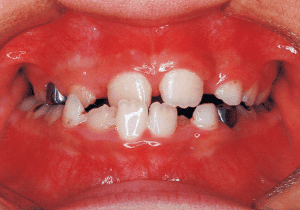

8 Beginning of 1st Phase 8-22-’88 7 years 1 month

9 After Phase 1 Treatment 8-21-’89 8 years 1 month

The Edgewise appliance was applied locally (8) and removed after 11 months (9). However, as the maxillary molar region gradually became crossbite, the maxillary arch was laterally expanded using a quad helix.